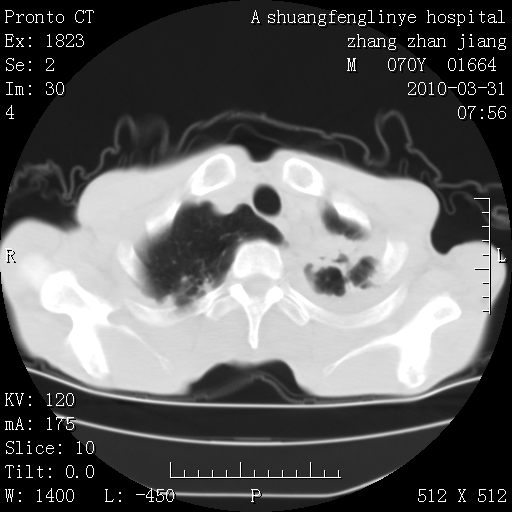

双上肺继发型tb并左上空洞形成,主动脉冠脉钙化。

支持:继发性肺结核伴空洞形成!建议纤支镜检查待出外周围型肺癌可能!

1)两肺上叶继发性肺结核并左肺上叶空洞形成。2)冠状动脉及主动脉钙化。